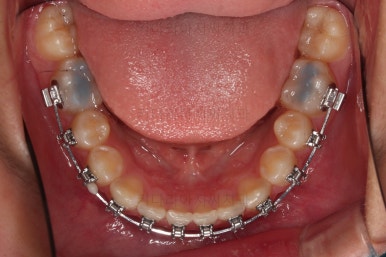

적절한 시기에 아랫니도 장치를 구성하고요.

과개교합 및 앵글씨 2급 부정교합 개선을 도와주는 장치도 보조적으로 활용해 주었습니다.

가지런한 느낌은 좋아졌고, 과개교합도 깔끔하게 개선이 되었습니다.

이제부터는 부정교합을 개선하면서 위아래 어금니 맞물림을 개선해 나갑니다.

교합이 개선됨에 따라 자연스럽게 중앙선도 좋아지고 있는 부분이 눈에 띄고요.

부정교합이 정말 많이 좋아졌습니다.